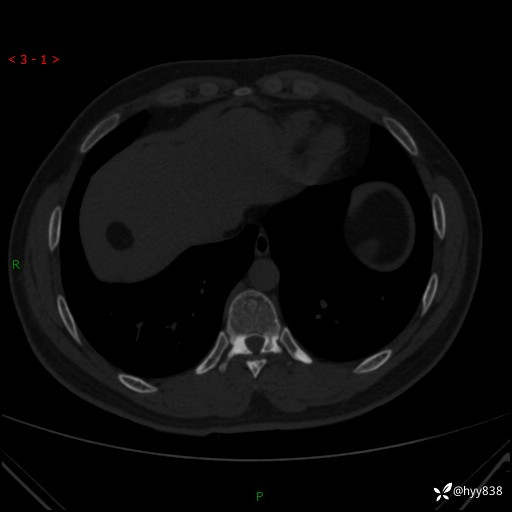

患者性别:男

患者年龄:28岁

简要病史:右肾肿瘤术后,常规复查

辅助检查:CT

临床诊断:右肾肿瘤术后

腹部CT+颅脑CT平扫